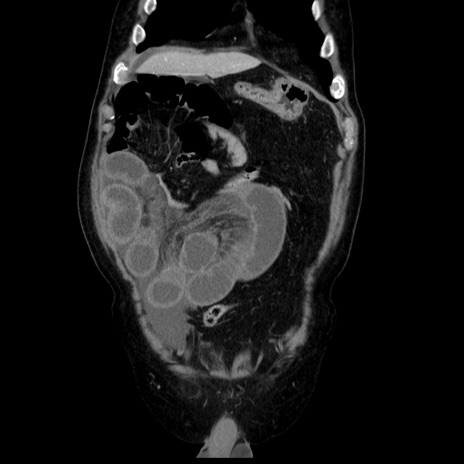

症例30(冠状断像)

【症例】80歳代男性

【主訴】臍周囲痛

【現病歴】約6時間前から臍下部痛が出現。次第に腹部膨隆・背部痛も生じてきたため来院。背部痛の場所は変化しない。

【身体所見】意識清明、BT 36.3℃、BP  131/87mmHg、P 87bpm、SpO2 100%(RA)、臍周囲自発痛・圧痛あり、反跳痛なし、自発痛部位に一致して板状硬あり、腹部膨隆、腸雑音減弱、CVA tenderness両側陰性。

【データ】WBC 19600、CRP 0.33